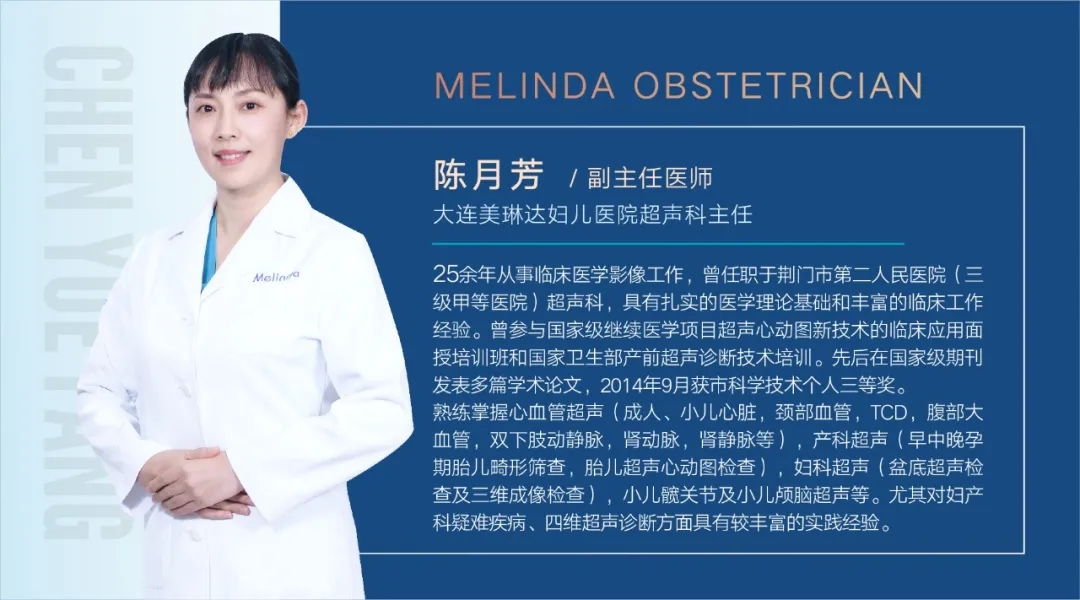

四维彩超的全称为四维彩色超声诊断仪,是目前世界上最先进的彩色超声设备。四维彩超的诊断资料有利于医生检测出各种异常,对于胎儿的成长发育做出准确的判断。那么四维彩超上的数据具体应该怎么看,美琳达妇儿医院四维彩超医生陈月芳和您说一说关于四维彩超的那些事儿!